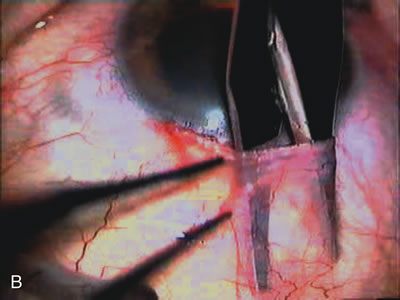

The inflammation associated with lens extraction at any site usually causes complete failure of a marginal functioning bleb. In addition, pressure reduction by medical means is usually minimal in these recalcitrant cases, and combined surgery is indicated. In the past, these cases were approached with large-incision ECCE, clear corneal cataract incision, and bleb revision. Drawbacks included those mentioned earlier for large incision clear corneal cataract extraction, and bleb revision is often associated with conjunctival buttonholes, wound leaks, subconjunctival hematoma, destruction of friable sclera, and associated hypotony. With the advent of modern-day cataract surgery, a phacotrabeculectomy is often possible adjacent to the failed filter (Fig. 7). The ability to combine cataract extraction with implant and filtration surgery all through the same small incision has greatly improved outcomes for patients with marginal preoperative filters. There are several other viable options in this case. If the surgeon elects to remove the cataract through a temporal clear corneal incision, the bleb may be revised or a new adjacent filter fashioned. As mentioned earlier, revising a failed filter is technically challenging. If the surgeon believes it is not feasible to revise the filter or fashion a new one, a glaucoma drainage implant is a reasonable option combined with temporal lens extraction.172

Fig. 7. Phacotrabeculectomy adjacent to a failed filter in cataractous eye. The ability to combine small-incision cataract extraction with trabeculectomy all through the same incision adjacent to the failed filter allows the surgeon to work in a familiar superior area. Avoiding incisions into the existing bleb decreases conjunctival buttonholes, hypotony, operating room time, and subconjunctival bleeding. A. Appearance of failed bleb with exposure of superior temporal quadrant gained with a corneal traction suture. B. Prepare a limbus-based conjunctival flap and a scleral flap. C. This bleb is at high risk to fail again justifying the need for MMC, 0.2 mg/cc applied on a pledget for 4 minutes. D. Insert the keratome and perform phacotrabeculectomy in the usual fashion.